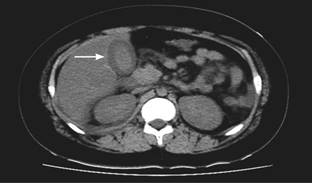

Al cuarto día de hospitalización, el paciente estaba taquipnéico y con disminución del murmullo vesicular en ambas bases pulmonares, lo que evidenció derrame pleural bilateral por ecografía torácica y tomografía computarizada de tórax. Se agregó aporte de oxígeno por cánula binasal. Debido a la persistencia del dolor abdominal, se realizó ecografía y tomografía abdominal donde se informó engrosamiento difuso de la pared vesicular (compatible con colecistitis alitiásica) y ascitis (Figura 1). En estudios de laboratorio se observó incremento de la lipasa (224 U/L), disminución de plaquetas (36,000 cel/mm3) y lactato de 2.6 mmol/L. Para el quinto día continuaba con dolor abdominal de intensidad moderada, además de vómitos y fiebre. Se observó con anasarca, dificultad respiratoria y elevación de la presión arterial (150/78 mmHg). En el manejo se agregó albúmina, diuréticos y captopril; además de metronidazol, vancomicina y ceftazidima.

Figura 1: Tomografía computarizada de abdomen en vista axial muestra líquido alrededor de vesícula biliar (flecha) con cambios reactivos de la misma, secundarios a inflamación sistémica.